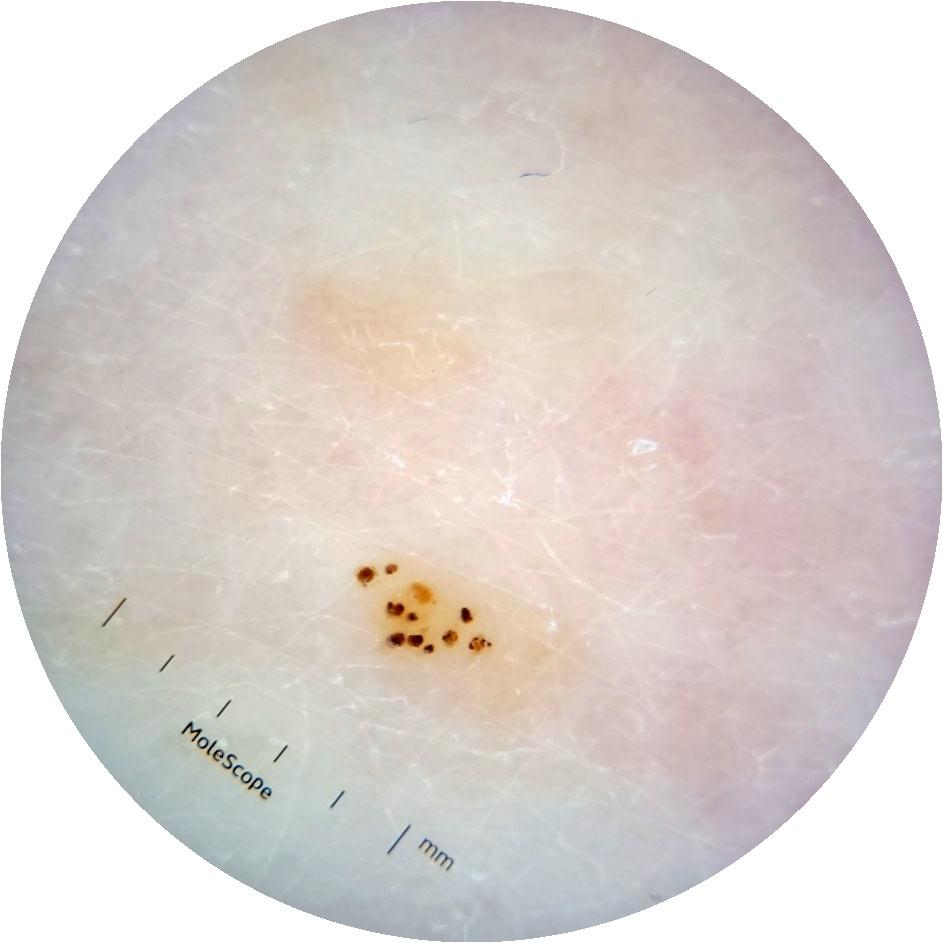

Clinical

Field Value

acquisition_day 264

age_approx 65

anatom_site_1 Trunk

anatom_site_2 Anterior trunk

anatom_site_general anterior torso

diagnosis_1 Benign

diagnosis_confirm_type single image expert consensus

image_type dermoscopic